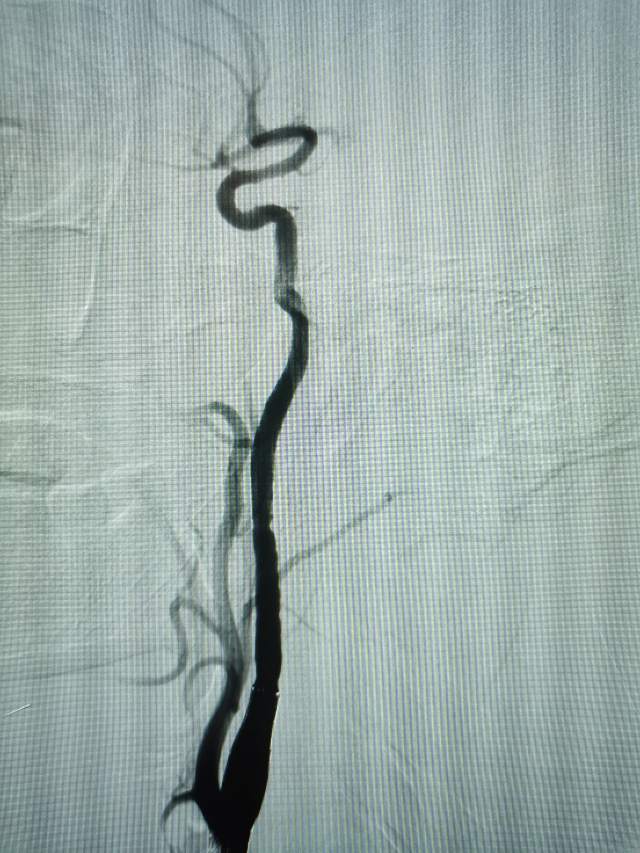

造影发现:

1、左侧颈内动脉起始部蹼

2、右侧颈内动脉起始部闭塞

既然口服抗血小板药物无效,那就只能外科干预,将起始部的瓣膜结构“蹼”机械性压在血管壁上,改善局部的血流紊乱和微栓子的形成。

下面开始对颈动脉蹼进行治疗